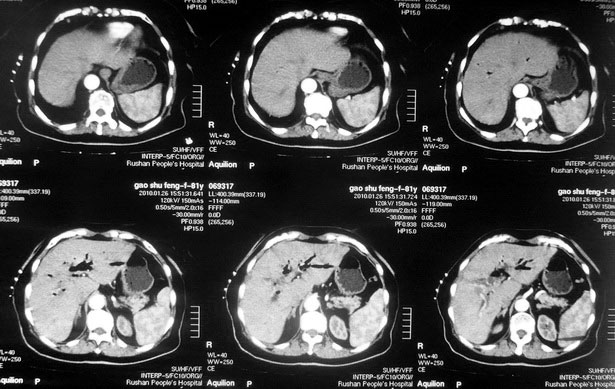

女,80岁既往有胆系手术史。近2月出现食欲不振,近20天出现畏寒发热,体重约下降10kg,体温一般在38℃左右。血常规wbc正常,中性比例88%,cea 10.3,afp、ca199均正常。做过一次肝穿,抽出约3ml仿佛脓性液体。这是她的增强ct扫描,请大家帮帮忙。另外想问问肝脓肿和胆管细胞癌的ct表现有什么区别。谢谢了。

【湘江一滴】化脓性胆囊炎及胆管炎,肝内胆管积气、积液、扩张;胆囊壁增厚、强化;胆周积液。未见肝内占位征象。

【shuiyuan】化脓性胆囊炎及胆管炎,肝内胆管积气、积液、扩张;胆囊壁增厚、强化;胆周积液.

肝脓肿动脉期呈明显环形强化或蜂窝状强化,胆管细胞癌动脉期强化不明显,且伴肝内胆管扩张。

【zenxisengming 】肝内胆管扩张积气,胆囊比环形增厚,胆囊周围渗出,未见占位性病变,应该是胆道化脓性感染

【sunbin】肝内见多个气体密度影伴气液面,胆囊壁增厚,胆囊周围低密度环绕,未见强化,支持化脓性胆管炎、胆囊炎。

最近复查ct,做了第二次穿刺抽脓,顺便做了涂片病理活检,结果找到恶性肿瘤细胞,诊断肝癌合并肝脓肿。看来大家都走眼了啊。